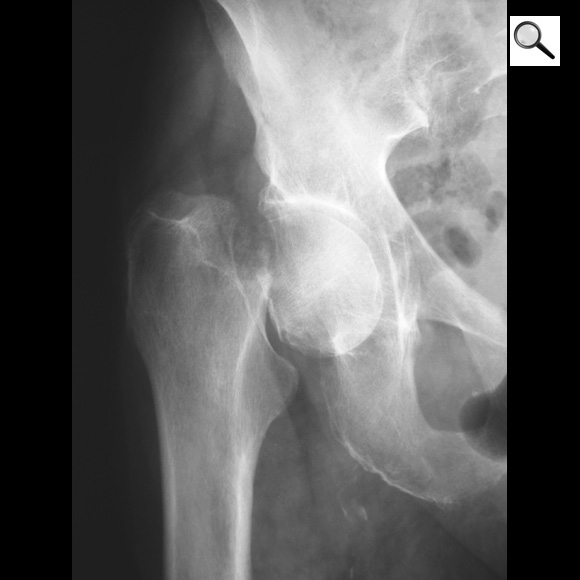

Quel est le stade Garden de cette fracture de l’ES du fémur? Quel est le risque évolutif principal?

Fracture ES fémur garden 4 car perte de contact entre fragments,

les travées osseuses sont normales

Risque max d’ostéonécrose aseptique